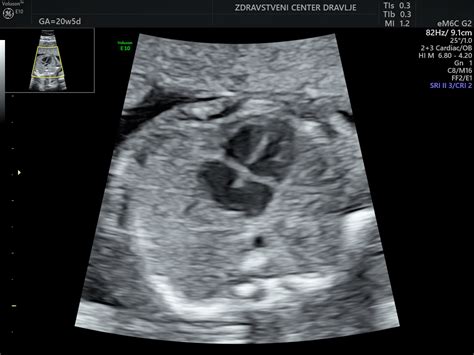

V tem obdobju se pričnejo razvijati tudi prstni odtisi, jezik in glasilke. Dojenček prične vaditi dihanje in požiranje plodovnice. Okoli 20. tedna nosečnosti, ko se opravi podroben ultrazvočni pregled, imenovan morfologija, je mogoče že opaziti spol otroka. Na morfologiji ginekolog pregleda razvoj posteljice in otroka ter oceni, ali obstajajo morebitni zapleti. V tem času mnoge nosečnice prvič občutijo nežne gibe svojega dojenčka, ki jih pogosto primerjajo s prhutanjem metuljevih kril. Ti gibi postajajo z nadaljevanjem nosečnosti vse bolj izraziti.